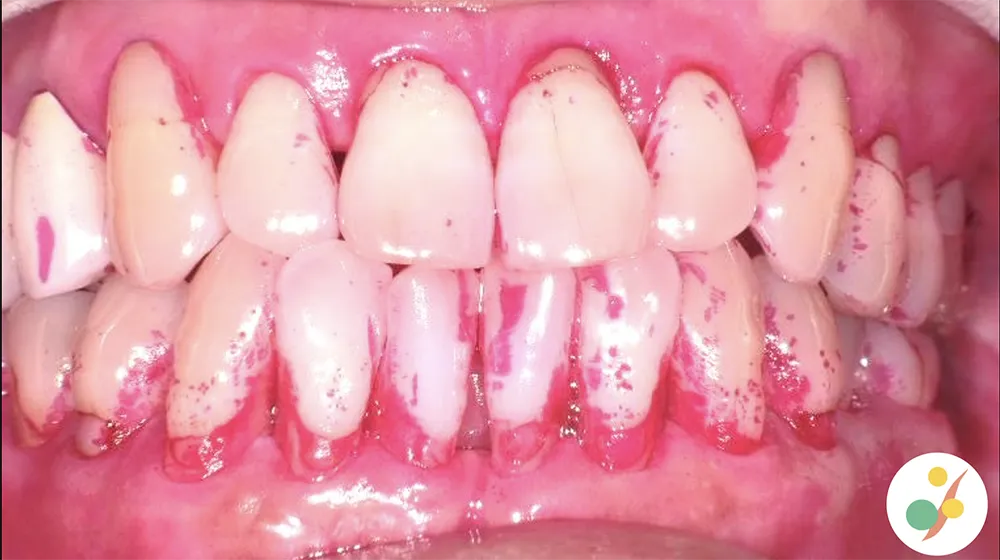

PCR

歯周病の原因となる歯垢の磨き残しを、染め出し液を使いながら確認する検査

視覚資料として提出する検査結果の一例